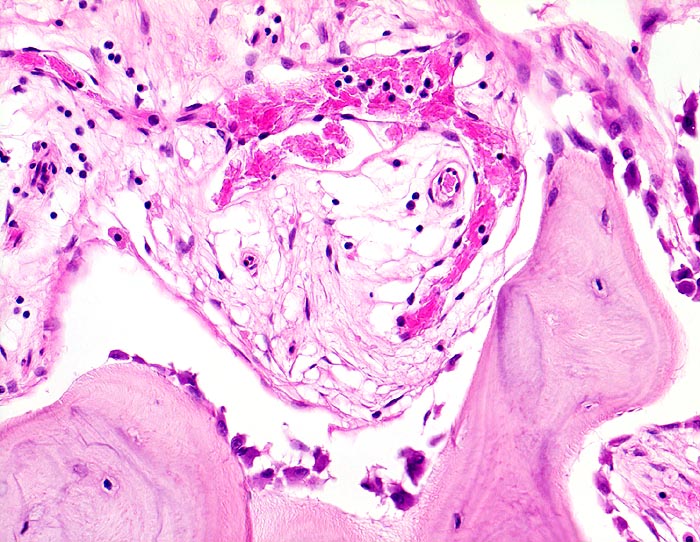

Morbus Paget des Knochens

Knochen, Tibia

Zone mit gesteigertem Knochenanbau. Das Spongiosabälkchen ist von einer Osteoblastentapete bedeckt, welche neuen Knochen anbauen. Das Mark zeigt eine lockere Fibrose mit vermehrten kapillären Gefässen.

Die Patientin hatte wiederholt über Knieschmerzen geklagt. Autoptisch zeigte das Kniegelenk eine leichte Arthrose. Aus der auffallend verdickten Tibia wurde eine Gewebsprobe zur Untersuchung entnommen.

200